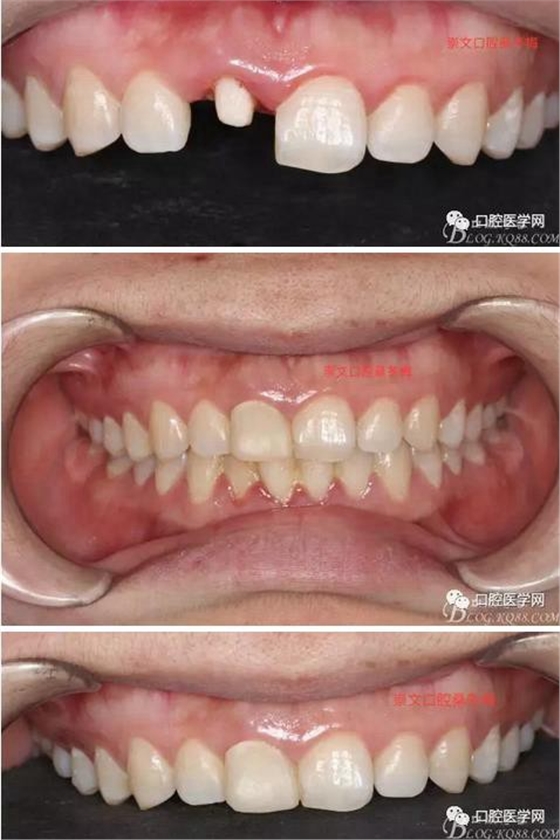

牙冠延長術(shù)后6周復(fù)診牙齦齦緣形態(tài)恢復(fù)良好,齦乳頭有些欠缺,患者著急永久修復(fù)。

纖維樁+樹脂核

樁道長14mm

備牙

戴牙